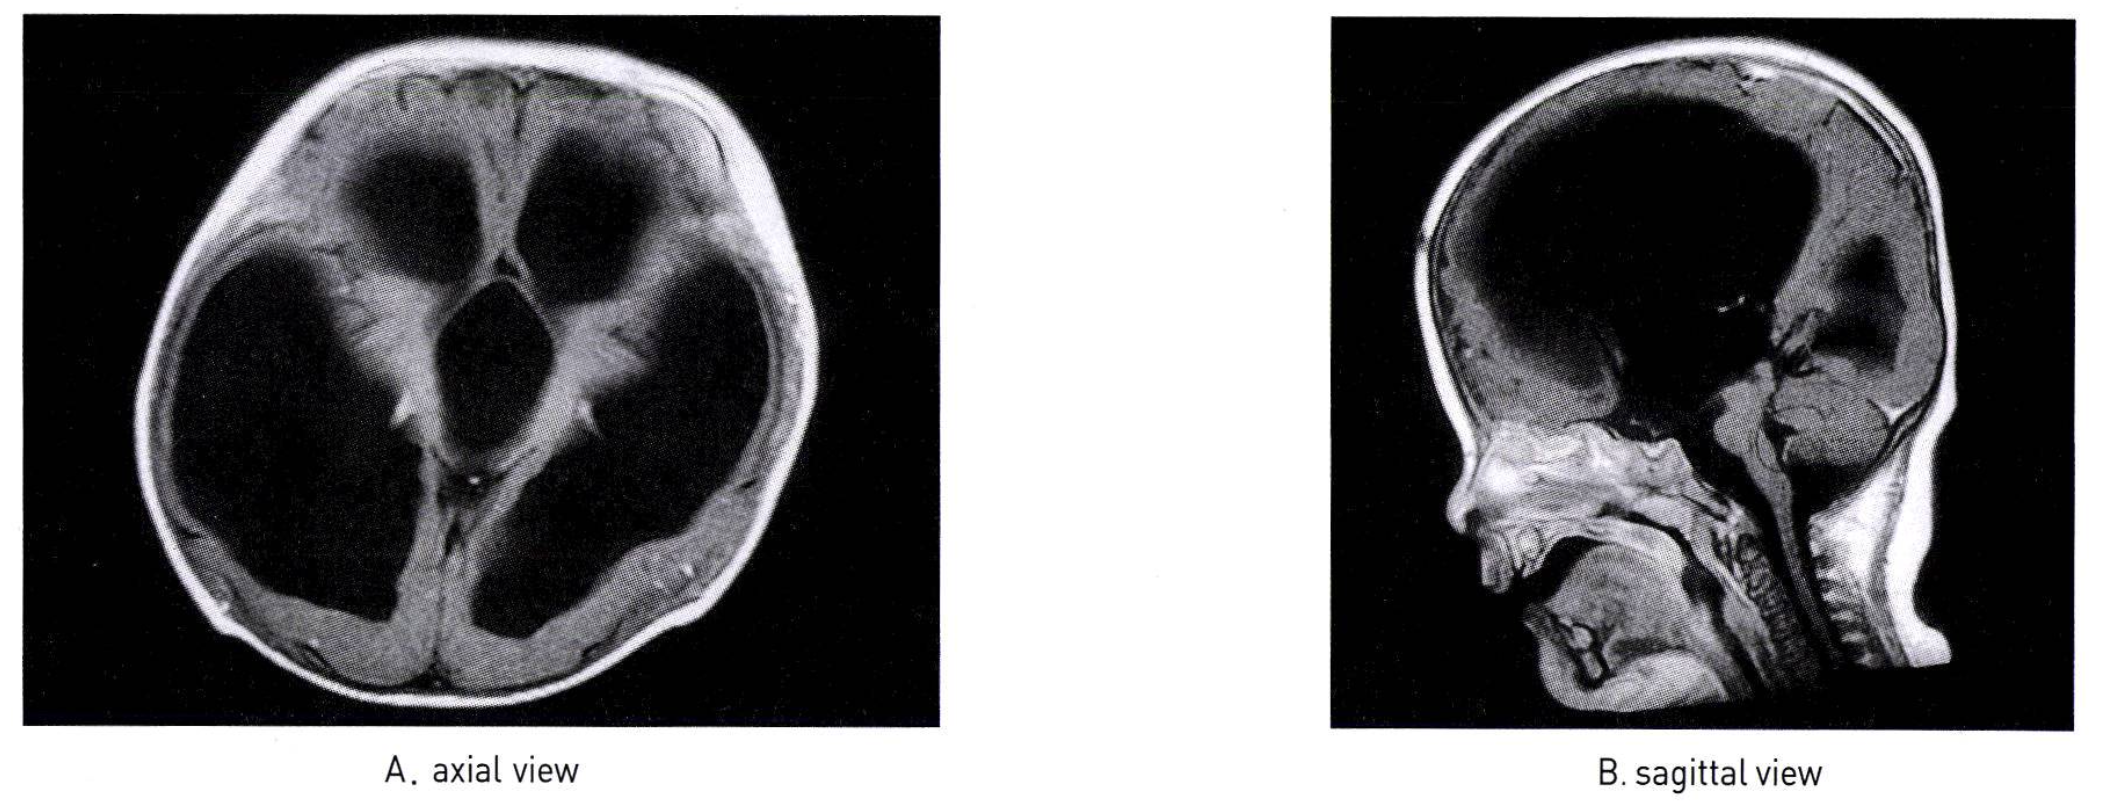

수두증 (Hydrocephalus)

• 정의: CSF 순환/흡수 장애 또는 CSF 과다 생성으로 인한 상태

• CSF 생리: CSF는 주로 맥락총 (choroid plexus)에서 생성. 흡수는 주로 거미막 융모 (arachnoid villi)에서 이루어짐

• 분류 및 원인

• 폐쇄성/비교통성 (Obstructive/Noncommunicating): 뇌실 내 순환 장애

• 원인: 수도관 협착 (Aqueduct stenosis) (m/c 소아 원인), 후두개와 병변 (Chiari, Dandy-Walker), 종양

• 임상 양상

• 영아: 머리 둘레의 급속한 증가, bulging fontanelle, setting-sun eye sign, transillumination

• 연장아: 두통, 구토, 기면, 성격 변화, 유두 부종

• 진단

• 영상 검사

• 초음파: 개방된 천문이 있는 영아에게 유용

• MRI: CSF 흐름 역학 및 원인 평가에 필수